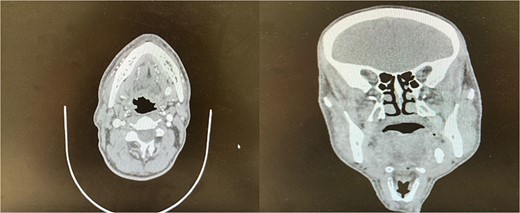

A 52-year-old male presented with a history of recurrent pain and swelling in the left submandibular region, suggesting sialadenitis. Ultrasound (US) identified a deeply located glandular stone measuring 2 cm. Subsequent CT confirmed the presence of a 21 × 18 mm fixed stone located deep within the gland parenchyma (Fig. 1).

Preoperative coronal and axial CT images showing a sialolith within the submandibular gland.